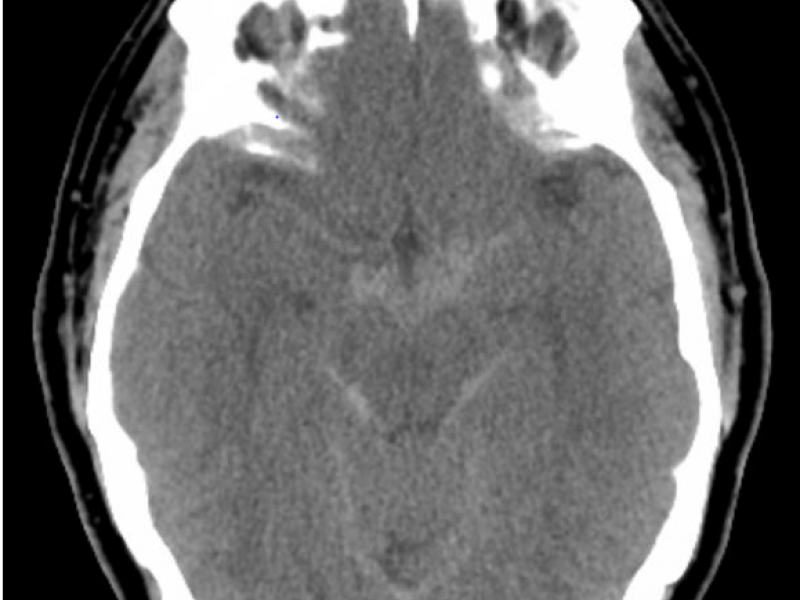

A 50 yo M presents to the ED w/ sudden onset severe headache